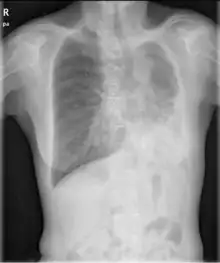

Chest radiograph of a woman with unilateral pulmonary agenesis | |

- Chest X-ray is effective in detecting the traits of lung herniation.[1] The unaffected side of lung tends to undergo hypertrophy, and move towards the empty space in the chest wall on the opposite side.[1] This herniation could be indicated by fluoroscopy.[1] With age increasing, the herniation progresses and ease its detection.[1]

- Electrocardiogram is useful in detecting dextrocardia, a possible outcome when agenesis is present on the right lung.[1] With empty space in the chest wall, the heart rotates in clockwise direction, shifting the location for apex beat occurrence.[1] Hence cardiac physical examination also helps as heart sounds is heard best at right chest with dextrocardia.[1][4] In the condition of left side agenesis, heart sounds will appear to be louder than normal.[1][4]

- Chest asymmetry, as a possible trait for pulmonary agenesis, is found to be more obvious in adult patients, especially in males.[4] Breast development in females tends to make it less obvious for the observance of asymmetry, though it could still be indicated by a more conical shape and slightly higher location of the breast on the affected side.[4]